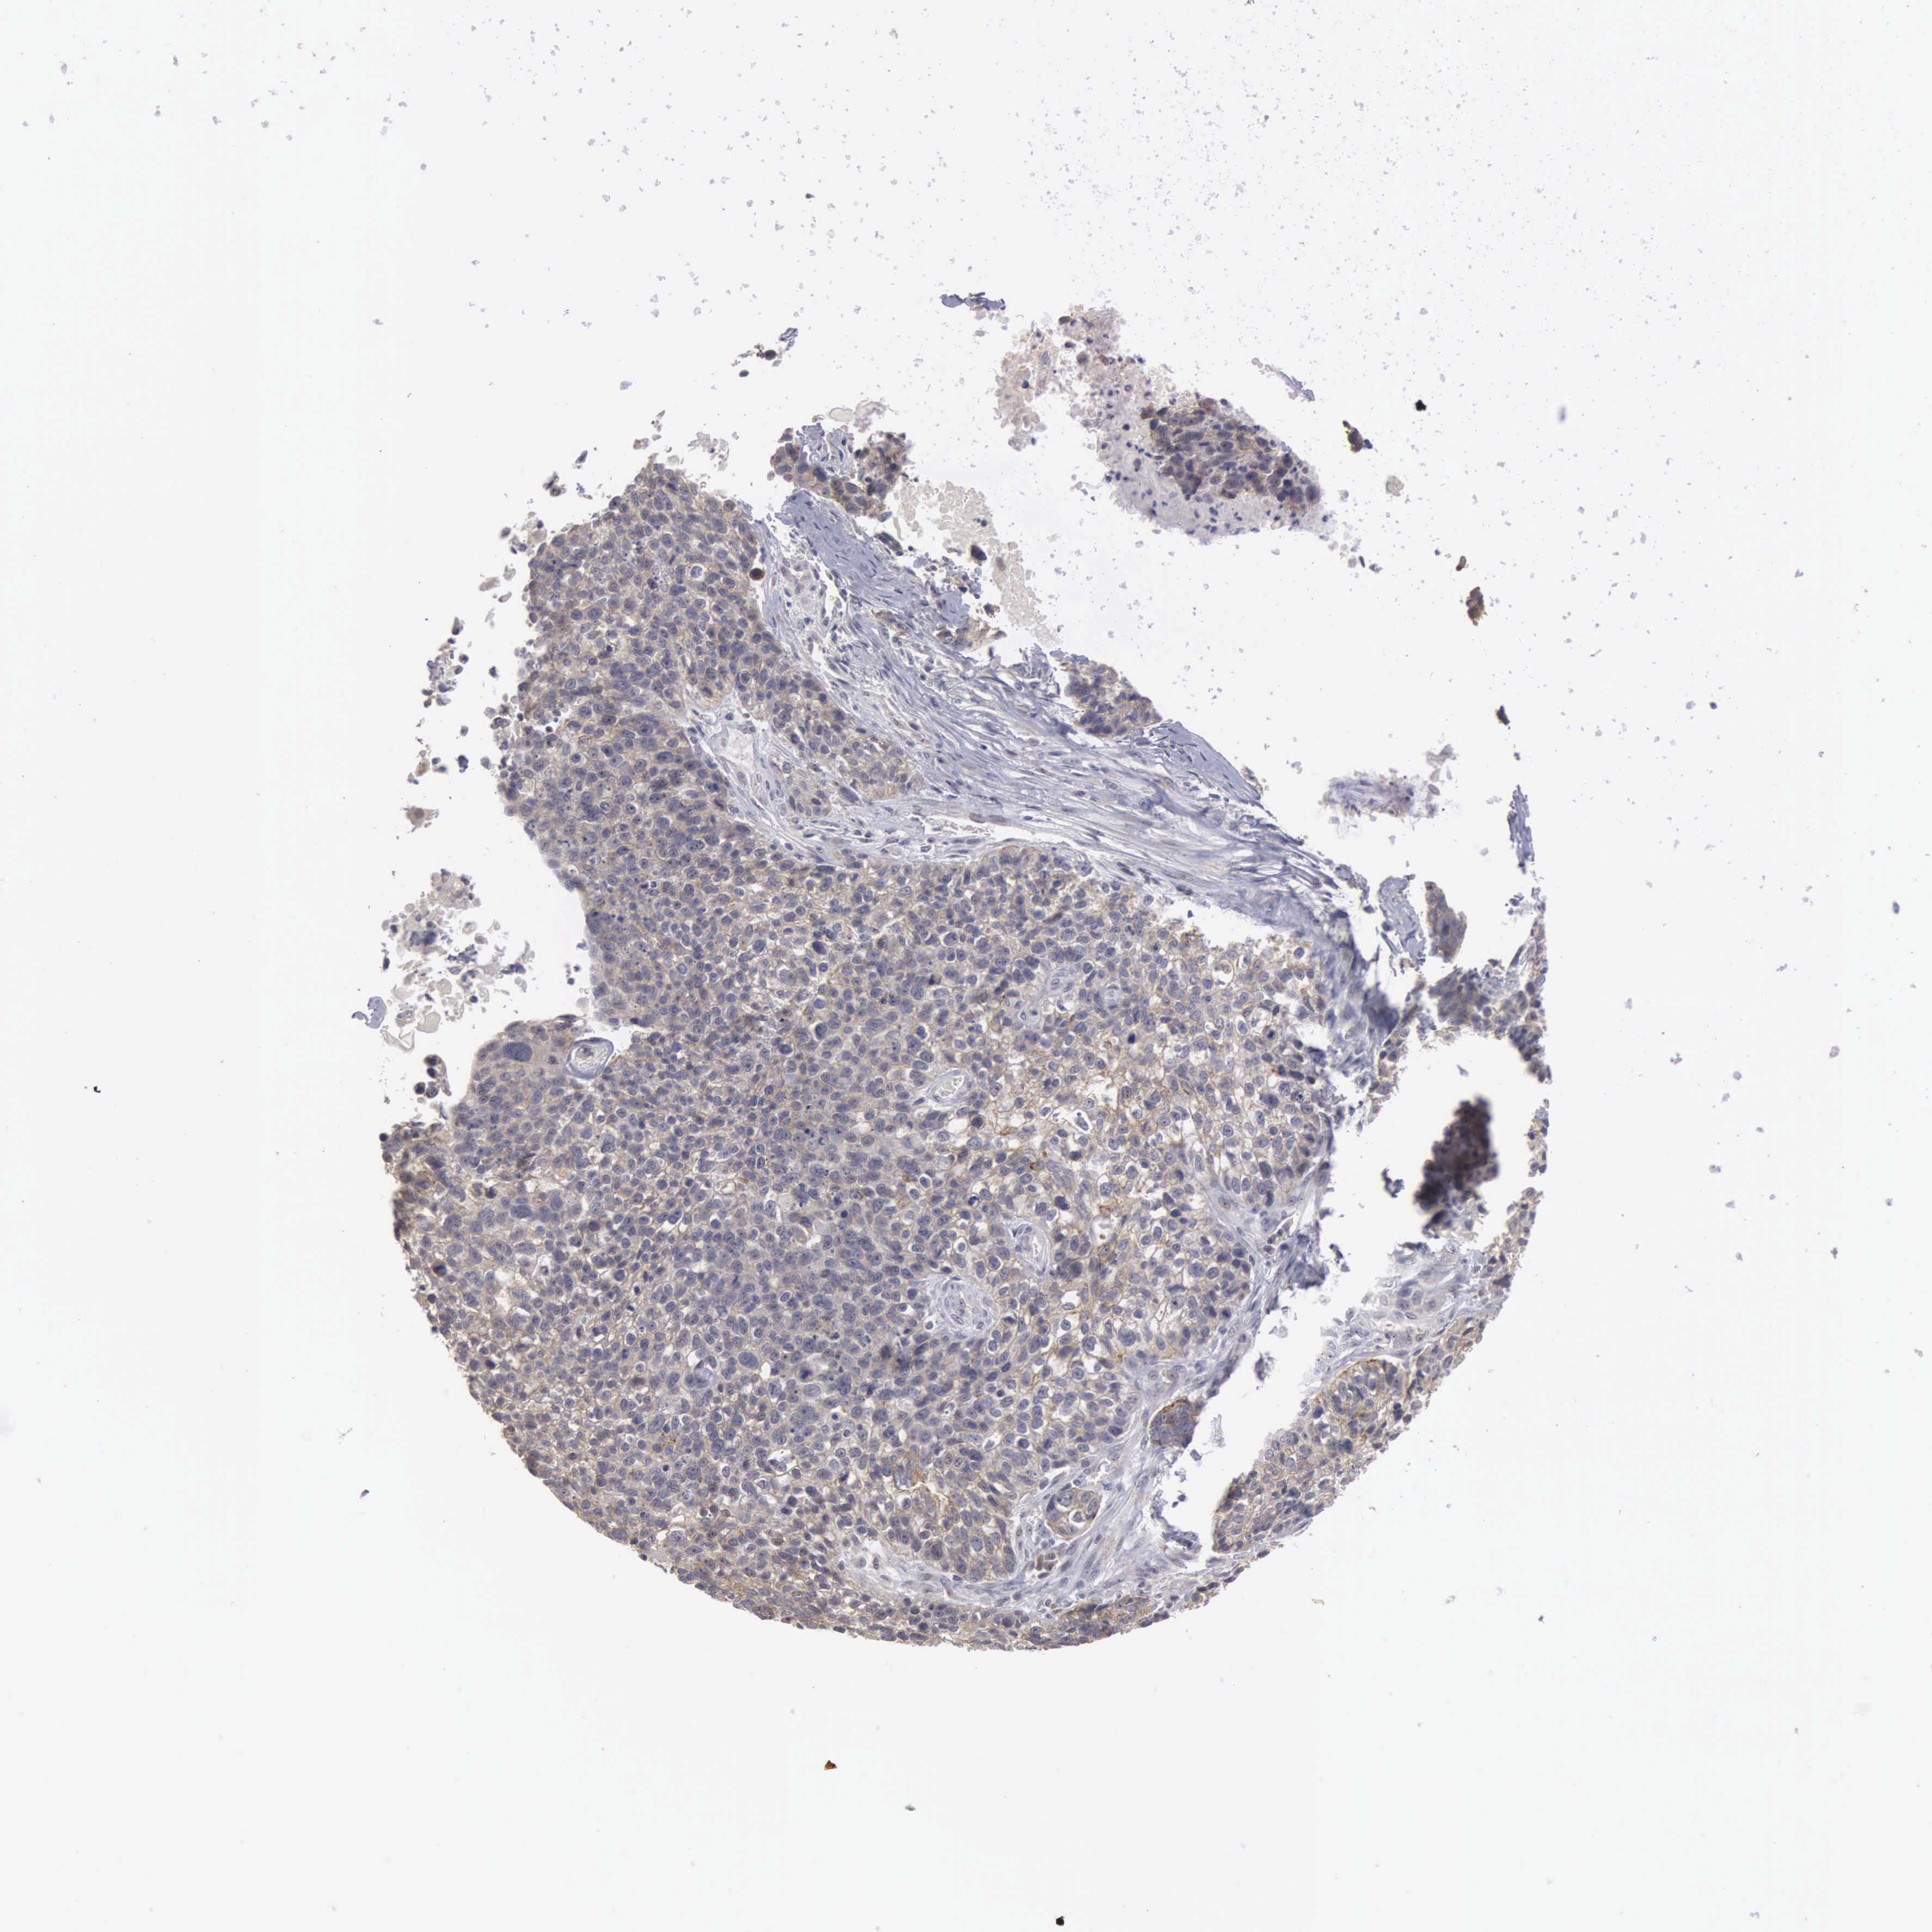

CANCER LUNG CANCER Show tissue menu

Lung cancer

Human cancer

Lung adenocarcinoma